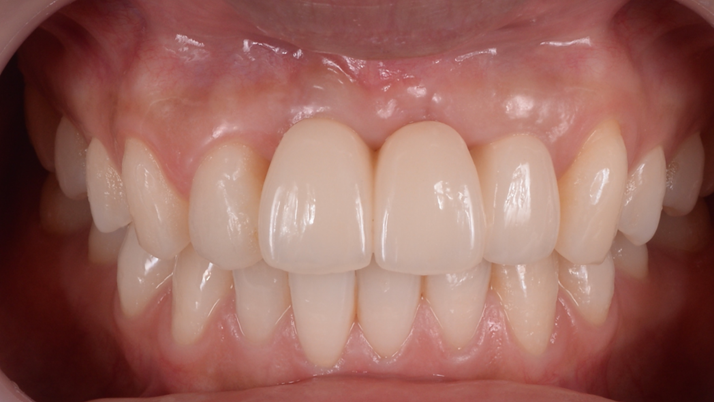

Clinical case: Patient-centered approach: treatment strategy for Root Membrane Technique & delayed implant placement

- Courtesy of Dr. Yoshiharu Hayashi, Japan -

“Advanced IntermezzoTM – one-piece solution for immediate placement & esthetic result in anterior region or narrow space.”